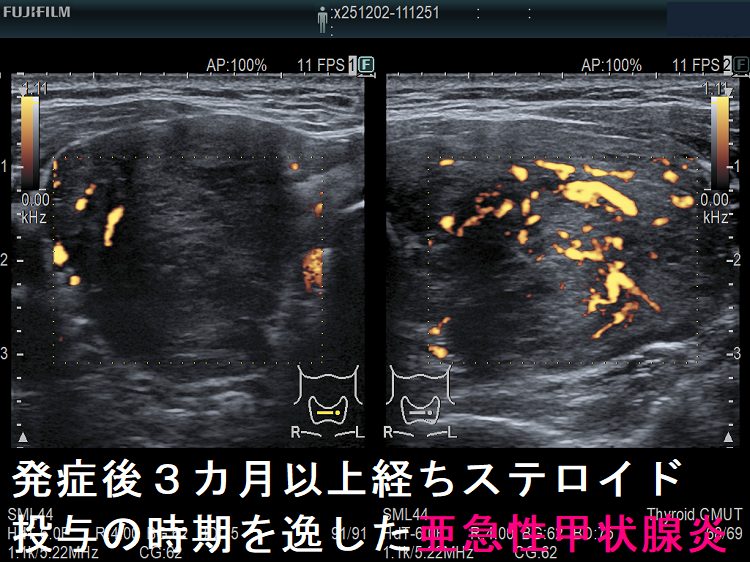

亜急性甲状腺炎には副腎皮質ホルモン剤(ステロイド剤)が劇的に効きます。たいてい服薬開始後2-3日で痛みも消え、熱も下がり、治ったような錯覚に陥ります。これにだまされ、服薬中止すれば(患者の自己判断・治療経験のない医者)、1週間以内に元の症状に戻り、最初から副腎皮質ホルモン剤(ステロイド剤)投与をやり直さねばなりません。最善の方法は、エコー所見が改善しているか確認しながら副腎皮質ホルモン剤(ステロイド剤)をゆっくり着実に減量するやり方です。(平均3-4か月は掛かります。)

- 発症後数か月以上経ち、ステロイド投与の時期を逸した場合